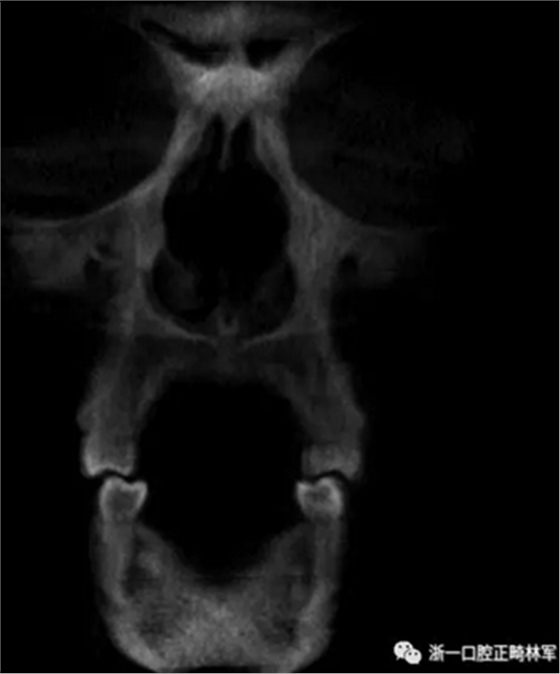

然而,CBCT成像也具有較大的限制:有限的分辨率,牙體組織的不準(zhǔn)確表現(xiàn),以及當(dāng)患者在咬合位或者完全牙尖交錯(cuò)位CBCT掃描時(shí),上頜骨和下頜骨牙齒之間發(fā)生的混合(圖1)。 這種混合使上頜骨與下頜骨牙齒的自動(dòng)分離復(fù)雜化,并且由于咬合解剖結(jié)構(gòu)和細(xì)節(jié)的不準(zhǔn)確而使人工分離變得困難。

圖1. 在CBCT中咬合時(shí)上頜牙齒和下頜牙齒咬合面的混合和咬合細(xì)節(jié)的喪失。